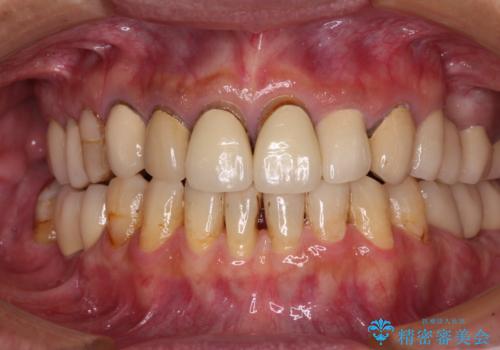

- 奥歯の大きな虫歯により歯が失われてしまい、大きく口を開けると歯がないことが周りの人に見えてしまうことを気にされていた患者様です。

前方の歯については学生時代の矯正治療の際、装置周りに多数の虫歯を作ってしまっていました。

奥歯の欠損部位については、インプラントにより咬めるようにし、その他の虫歯については審美補綴治療を行います。

右上の犬歯は歯肉退縮が著しく、歯肉移植による根面被覆を提案しましたが、しばらくは様子を見たいとのことでした。